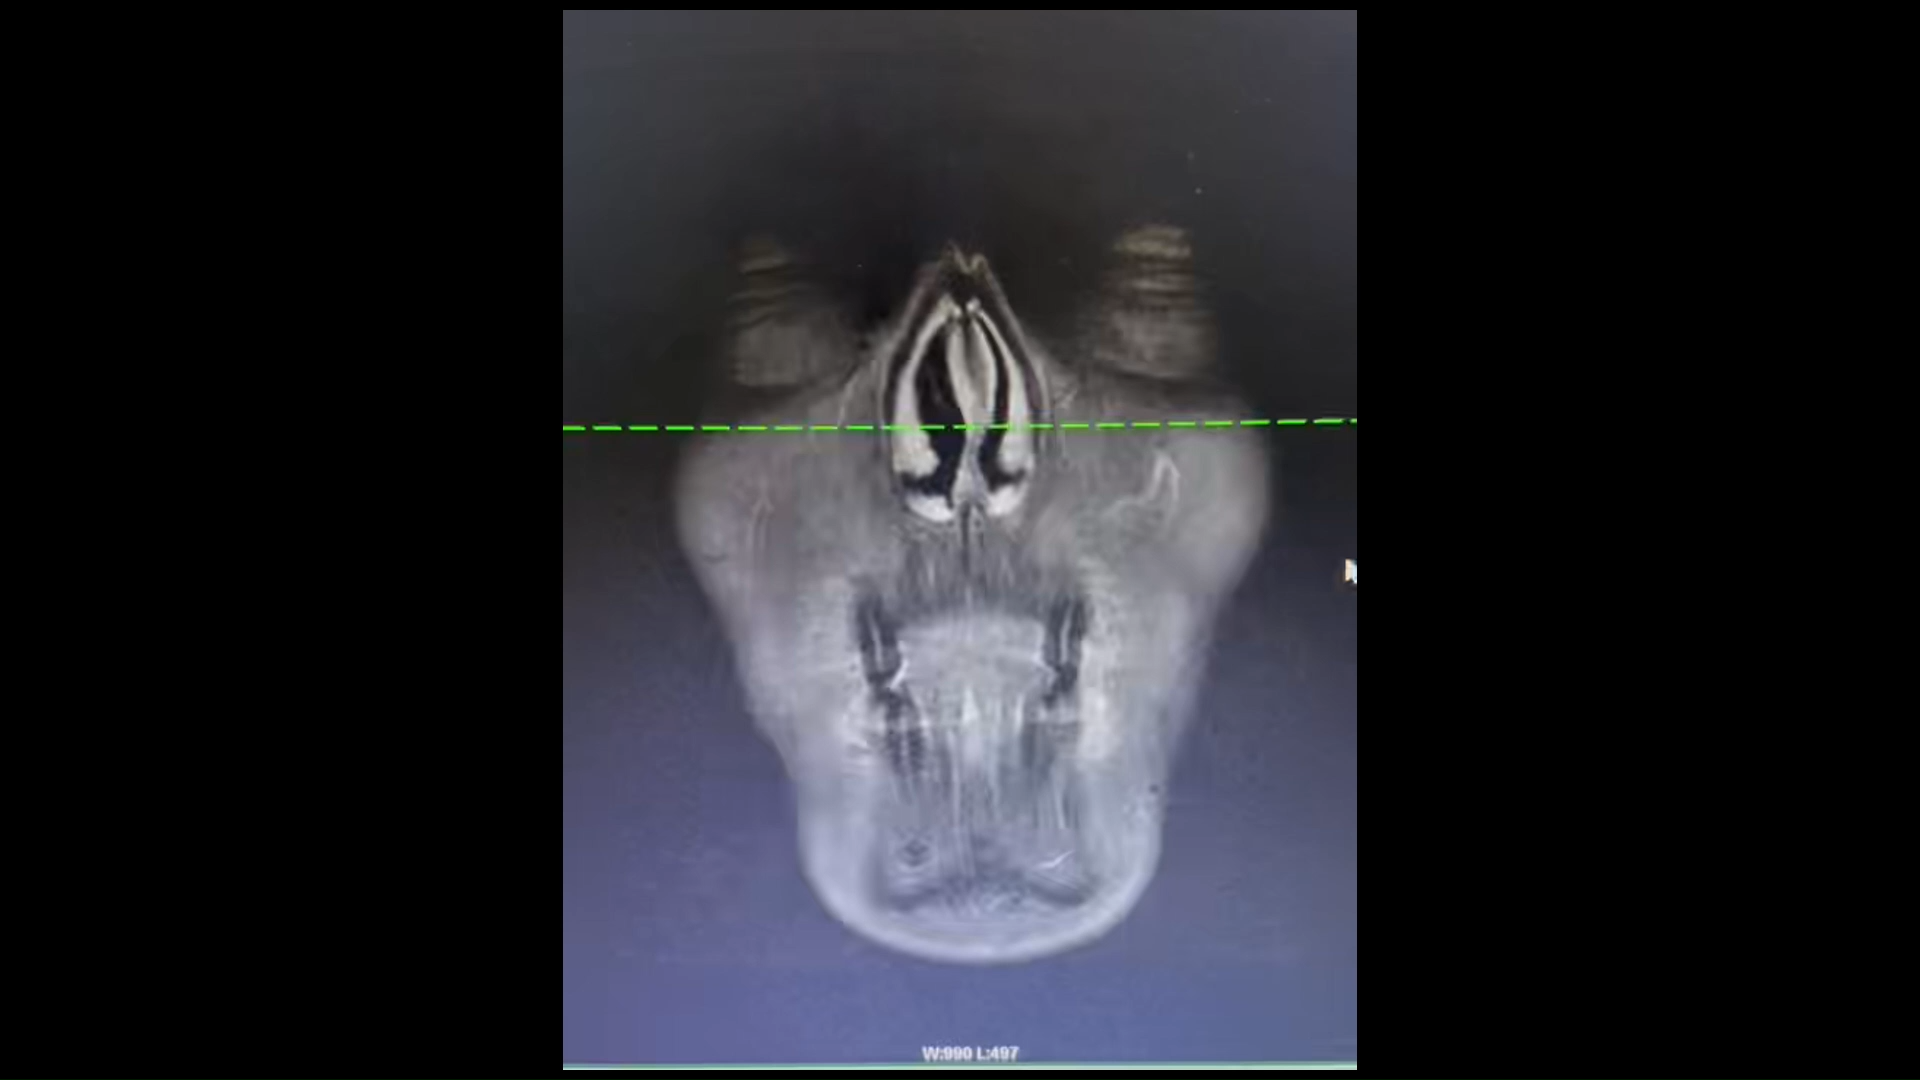

病例颞下窝肿物 鳃裂囊肿?皮样或表皮样囊肿?淋巴管瘤?